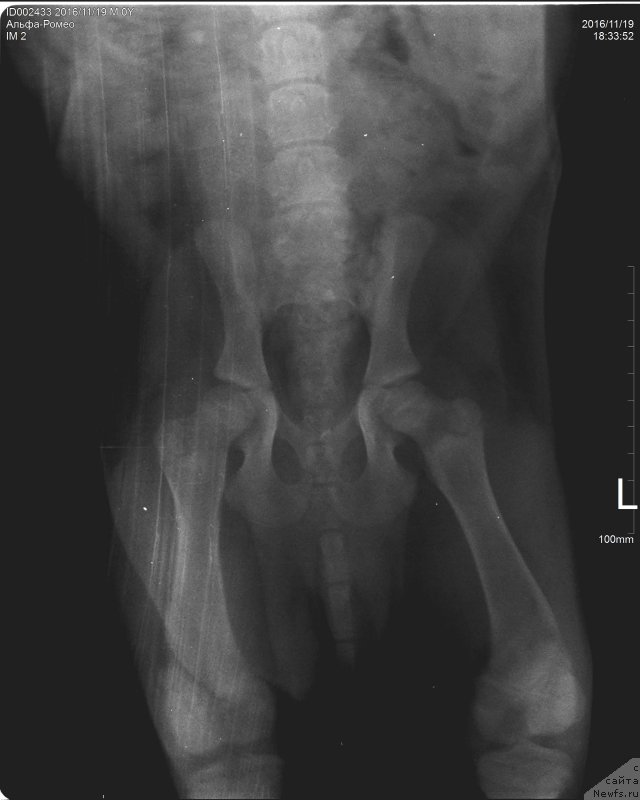

Браунблад МСК Альфа-Ромео Голд Бадди (Brownblood MSK Alfa-Romeo Gold Baddy)

Браунблад МСК Альфа-Ромео Голд Бадди (Brownblood MSK Alfa-Romeo Gold Baddy)